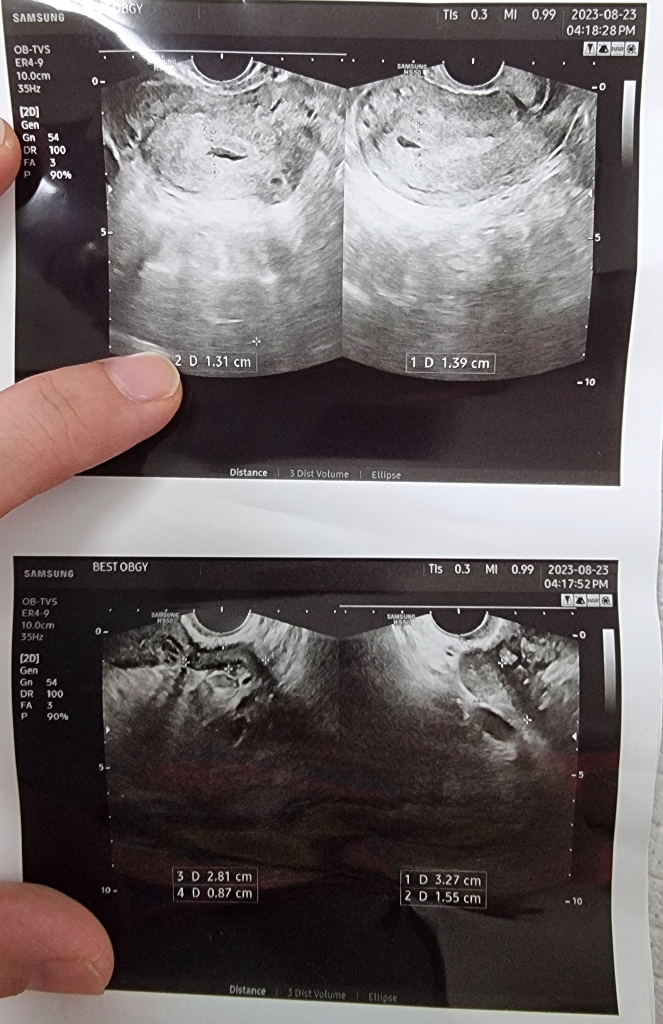

23일 어제날짜로 다른병원 다녀왔는데

주수대로면 5주차인데..아기집은 안보이고

피고임만 보인다고 하더라구요..

피검하고 왔는데 450 나왔습니다..

자궁외임신 가능성이 많이 높은건가요..?